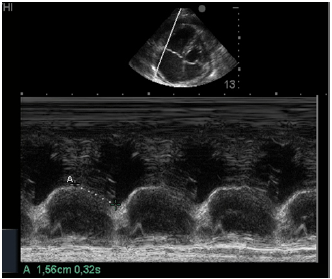

Na insonação cardíaca beira-leito, a mensuração da excursão do anel da tricúspide (TAPSE) resultou em 1,56 cm como demonstrado na imagem apresentada.

Isso significa ventrículo direito